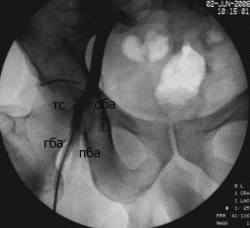

Иллюстрации 4, 5. Обработка изображения с увеличением.

данное наблюдение не совсем корректное. Обезыствления вен более похоже на ненаучную фантастику. Ход и локализация обезыствленных сосудов соответствуют проекции общей бедренной артерии и ее бифуркации на поверхностную и глубокую артерии(в 90% случаев она расположена ниже головки бедреннной кости. Для наглядности привожу несколько примеров.